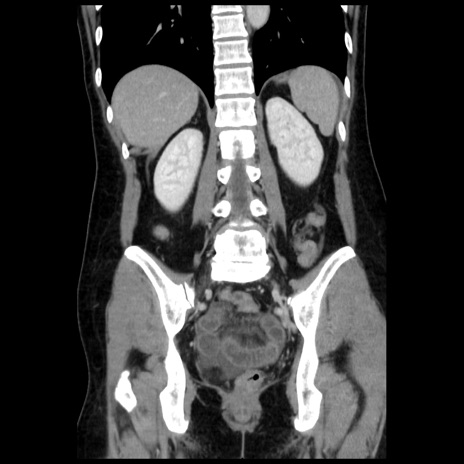

症例10(冠状断像)

【症例】 50歳代女性

【主訴】 腹痛

【現病歴】前日生レバーを食べた。今朝に排便あり。 昼前に突然発症の腹痛を生じ、当院救急外来を受診した。

【既往歴】 子宮筋腫にてで子宮全摘後

【身体所見】 意識清明、腹部:平坦、軟、下腹部やや左を中心に圧痛・反跳痛あり、筋性防御あり

【データ】WBC 7800、CRP 0.07